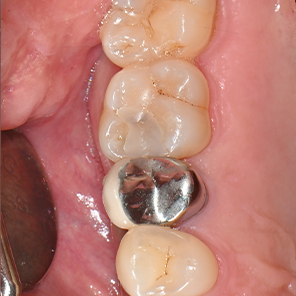

치과의사의 손길로 빚어내는, 섬세한 치아 수복

레진빌드업은 치과의사가 구강 내에서

직접 치아의 형태를 세심하게 만들어나가는 수복 방식입니다.

자연치아의 구조를 모방(biomimetic) 하여

신중하게 접착하는 과정을 거치며,

본래 치아와 조화롭게 기능할 수 있도록 돕습니다.

레진빌드업, 이러한 가치를 담아 진료합니다

보존 중심 접근 │ 자연치아의 건강한 부분을 가능한 보존하는 것을 목표로 진료 계획을 세웁니다.책임감 있는 진료 │ 상담부터 마무리까지, 모든 과정을 치과의사가 직접 세심하게 진행합니다.정밀 접착 과정 │ 치아와 재료가 긴밀하게 결합될 수 있도록 세심한 접착 단계를 거칩니다.자연스러운 조화 │ 주변 치아와의 색상이나 형태 등 전체적인 조화를 고려하여 수복을 진행합니다.